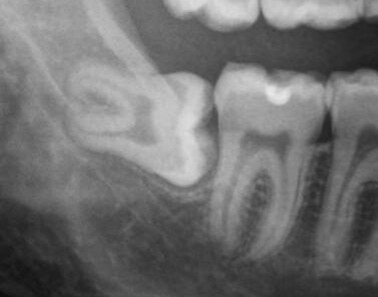

Горизонтальное положение зуба мудрости, одно из самых неприятных, потому что  у зуба нет ни одного процента на нормальное прорезывание, так еще для того, чтобы его удалить, порой приходится убирать всю вышележащую кость.

Типичный случай. Восьмёрка ещё не прорезалась, но мы можем увидеть вектор её прорезывания, на котором видно, что места ей явно не хватит, она будет упираться в семёрку и сдвигать её, а затем и весь зубной по принципу домино

Какое тут может быть решение? Если мы видим такую картину, то решение только одно - удаление зуба. Бояться этого не нужно, зуб все равно не сможет прорезаться в обход рядомстоящего и даже если он каким-то чудом встанет в зубной ряд, жевать он не будет, так как антагониста у него нет, соответственно никакой функции он не несёт.

Также такие зубы очень сложны для качественной чистки из-за своего дальнего расположения, что представляет собой бомбу замедленного действия